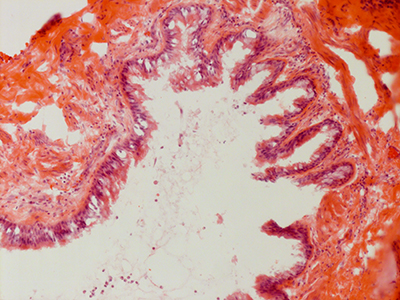

31 Year Old Adult Human Lung D003 H&E